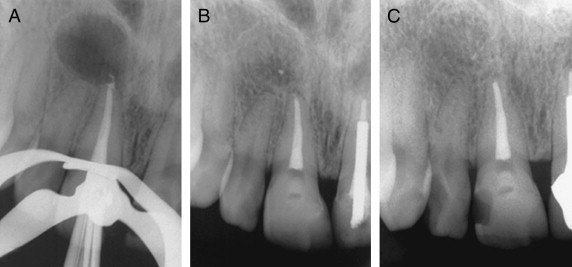

What is in the left image?

Radicular cyst

(aka periapical cyst)

What is this type of globulomaxillary radiolucency?

Periapical granuloma

What is this radiolucency?

(hint: 2nd most common globulomaxillary radiolucency)

What is this 3rd most common type of globulomaxillary radiolucency?

Lateral periodontal cyst

Is this a lateral periodontal cyst or radicular cyst?